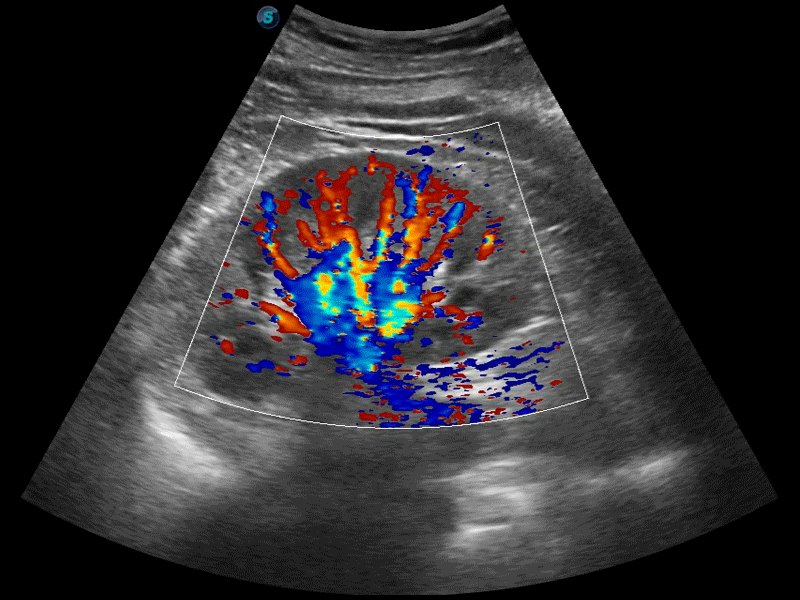

高分辨率血流成像技術(shù)提高了對(duì)低速血流信號(hào)的檢測(cè)能力。在提高空間分辨率的同時(shí),也克服了血流外溢現(xiàn)象,為用戶提供更加真實(shí)的血流動(dòng)力學(xué)信息。